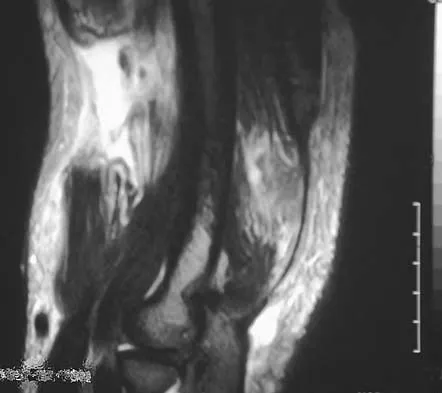

Question 81High Yield

An 18-year-old boy has had pain in the right knee for the past 6 months. Examination reveals some fullness behind the knee but no significant palpable soft-tissue mass. There is no effusion, and he has full knee range of motion. The remainder of the examination is unremarkable. A radiograph and MRI scans are shown in Figures 33a through 33c, and biopsy specimens are shown in Figures 33d and 33e. What is the most likely diagnosis?

Explanation